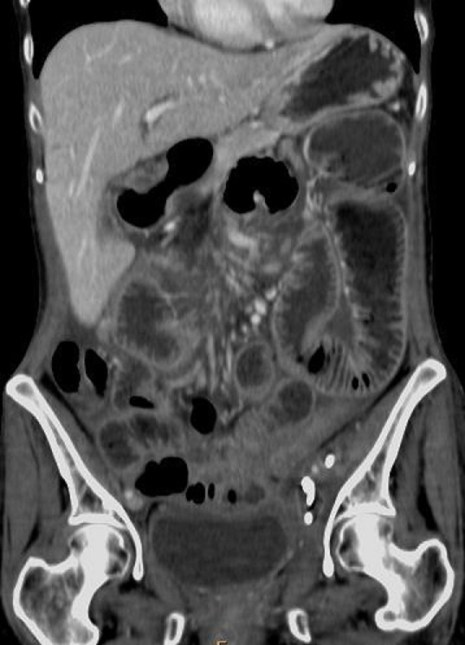

Lipoma intestinal: frecuente como punto guía o cabeza de invaginación en el instestino delgado. Aquí presentamos un caso de lipoma intraluminal en el colon, que producia obstrucción y cambios inflamatorios en el colon ascendente.